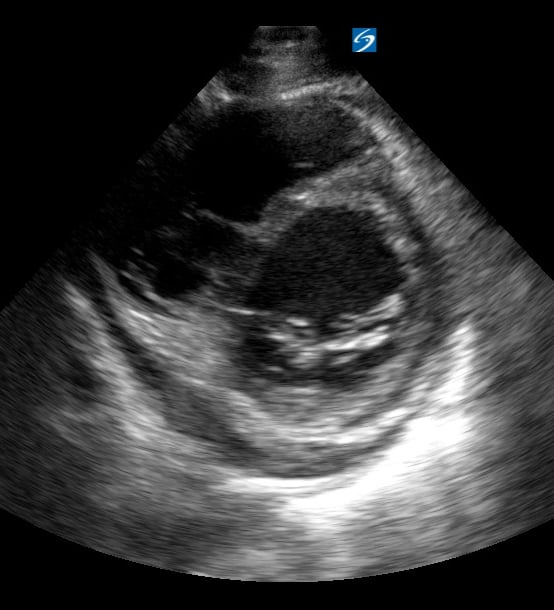

Pericardial effusion in cardiac ultrasound refers to an abnormal accumulation of fluid within the pericardial sac, the double-layered membrane surrounding the heart. This condition can impede the heart’s ability to fill and pump blood effectively, potentially leading to cardiac tamponade, a life-threatening emergency. Early detection through echocardiography is crucial for timely medical intervention and improved patient outcomes.

Utilizing medical ultrasound, healthcare professionals can accurately identify and quantify pericardial effusions, assessing their size, location, and hemodynamic impact. Ultrasound imaging provides real-time visualization of the fluid build-up, enabling precise diagnosis and guiding potential therapeutic procedures such as pericardiocentesis. This non-invasive technique is indispensable for managing cardiac health and preventing severe complications.